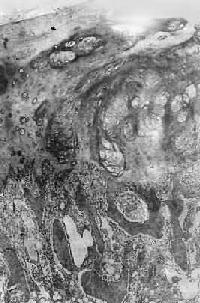

镜下观,肿瘤的分化程度差异很大,分化好的软骨肉瘤在镜下易误诊为软骨瘤,但在肿瘤的边缘可以找到瘤细胞的异型性,如核肥大、深染,出现较多的双核、巨核和多核瘤巨细胞,并可见明显核仁(图17-4)。在分化差的软骨肉瘤则上述瘤细胞的异型性很明显,核分裂像也多见。软骨肉瘤的基质可为与一般透明软骨相似的透明基质,也可为粘液样基质,常见于恶性程度高的软骨肉瘤。

图17-4 软骨肉瘤

软骨细胞大小不等,有的较大。许多细胞有肥硕的胞核,有的有双核 ×175